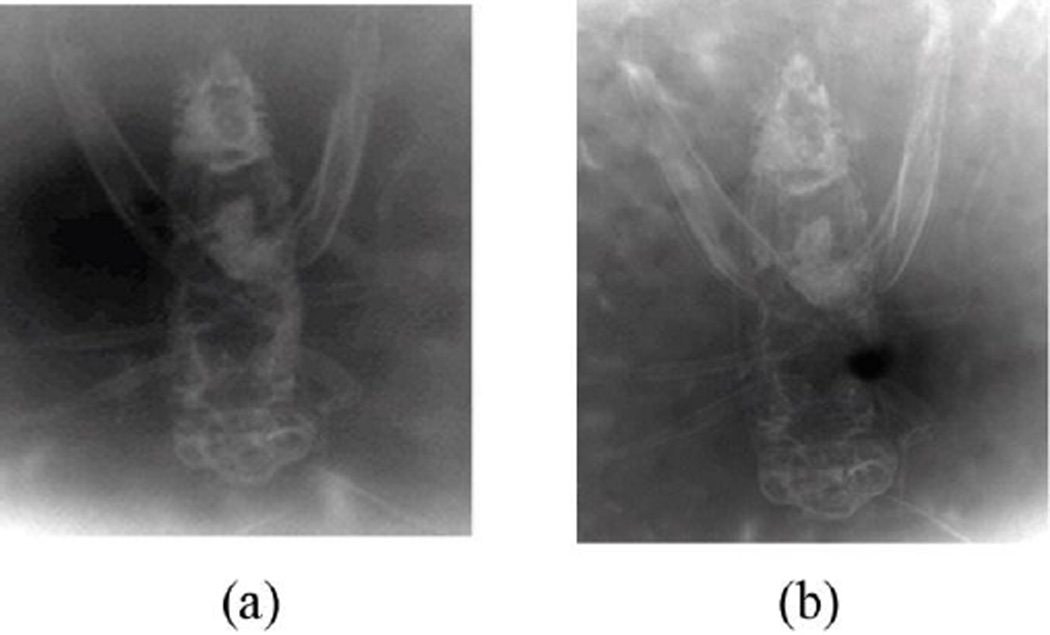

A conventional absorption image, shown in Figure 17(a), was acquired with an insect at a distance of R1 = 40 cm from the source, with the image plate placed just behind the object at a distance of R2= 2 cm. The phase contrast image shown in Figure 17(b) was taken with the detector displaced to a distance of 67 cm from the insect, keeping R1 = 40 cm.

Figure 17.

(a) Contact image of the cricket (detector placed against the insect). (b) Phase-contrast image of a cricket with detector placed 67 cm from the insect. The edges of internal structures are clearly visible even though a low-resolution detector was employed

The phase contrast image shows not only the internal structures (due to absorption) but also shows clearly defined boundaries evidencing edge enhancement. Some of the improvement is due to the smaller effective pixel size due to the magnification; however there is visible edge enhancement.